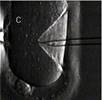

На рисунке 8 изображена ультразвуковая картина переноса эмбрионов: зеленым – движение катетера в полость матки через шейку матки:

Рисунок 8.

Ультразвуковая картина переноса эмбрионов*